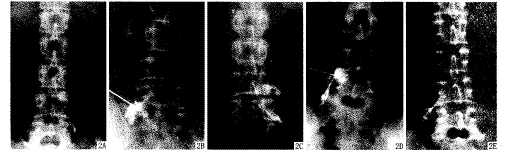

【摘要】 目的 探讨神经根造影封闭对腰椎间盘突出症和椎管狭窄症的诊疗意义。方法 对59例根性症状明显者作选择性神经根造影。结果 6例穿刺失败,41例显影异常,于造影后即作封闭,观察6个月无感染和神经根损伤。神经根异常图像在椎间盘突出多为椎体上缘或小关节突内缘充盈缺损中断,椎管狭窄时以边缘不整像为主。根据封闭提示对多节段椎间盘突出作单节段有限手术。结论 该方法可作为椎间盘突出及椎管狭窄的影像和功能诊断手段,封闭有一定治疗作用。